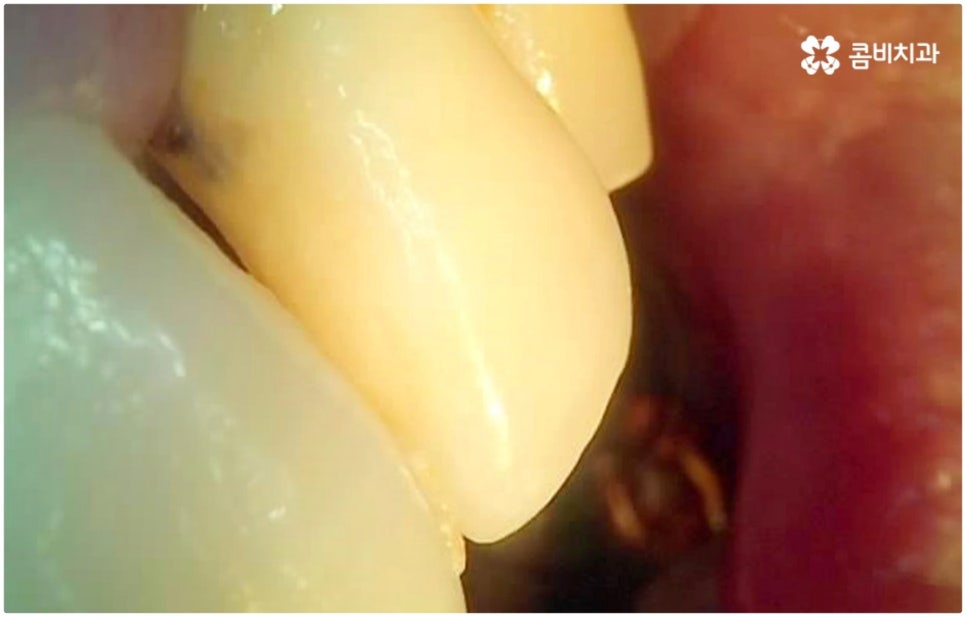

하지만 여기서 주의하셔야 할 점은 누구나 발치후 임플란트 를 즉시 식립할 수 있는 것이 아니라 바탕이 되는 잇몸뼈의 양이 충분하고 기존에 염증과 같은 잇몸 질환이 없는 분들의 경우에만 이용할 수 있는 방법이기 때문에 3D CT 등 정밀 분석 기계로 환자분들의 상태를 정확하게 진단한 후에 결정해야 한다는 거예요.

즉, 해당 분야의 임상 경험이 풍부한 숙련된 의료진분들이 계신 치과에서 자신이 발치후 임플란트 즉시 식립 방식이 가능한지 부터 확인하실 필요가 있는데요. 만약 다양한 이유로 인해 발치 후 즉시 심는 것이 불가능한 케이스라고 한다면 상황에 맞게 뼈이식, 상악동 거상술, 잇몸 질환 치료 등 선처치들을 먼저 해 주고 나서 충분한 회복 기간을 두고 임플란트 시술을 진행해야 식립 성공률 및 지속 가능성을 높일 수 있습니다. 이렇게 환자분들 각각의 상황을 고려하지 않은 채 발치 후 즉시 식립을 무리하게 진행하게 되면 임플란트의 위치를 제대로 고정하는 데 어려움이 있어 해당 치아로 잘 씹을 수 없게 되고 얼마 지나지 않아 다시 쓰러지거나 주변 치아와 잇몸에 압박을 가해서 지속적으로 좋지 않은 영향을 주게 되는 등 문제가 커질 수 있으니 주의하실 필요가 있어요.

임플란트 치아는 사후 관리만 잘 해 준다면 거의 반영구적으로 사용이 가능하기 때문에 이를 위해 임플란트 치아에 갑작스럽게 너무 큰 힘이 가해지지 않도록 조심하고 정기적으로 치과에 내원하여 스케일링 치료 및 검진을 받는 습관을 들인다면 보다 바람직할 거예요. 만약 제대로 관리해 주지 못하면 임플란트가 부러질 수도 있고 임플란트 주위염과 같은 혹시 모를 부작용을 겪을 수도 있는데요. 이는 임플란트 치아 자체의 수명을 짧게 할 뿐 아니라 치조골을 녹이면서 임플란트 치아가 흔들리고 결국 빠지게 만드는 등 더 큰 문제로 이어질 수 있기 때문에 주의하실 필요가 있습니다. 이렇게 잇몸뼈 상황이 안 좋아지게 되면 혹여 재수술을 해야 한다고 했을 때 처음 식립시 보다 훨씬 어려움이 커지게 되고 정도가 심각한 경우 재수술이 아예 불가능 하게 될 수도 있으므로 특히 주변 잇몸 건강에 신경써서 꾸준히 관리해 주시길 권유드리고 있어요.